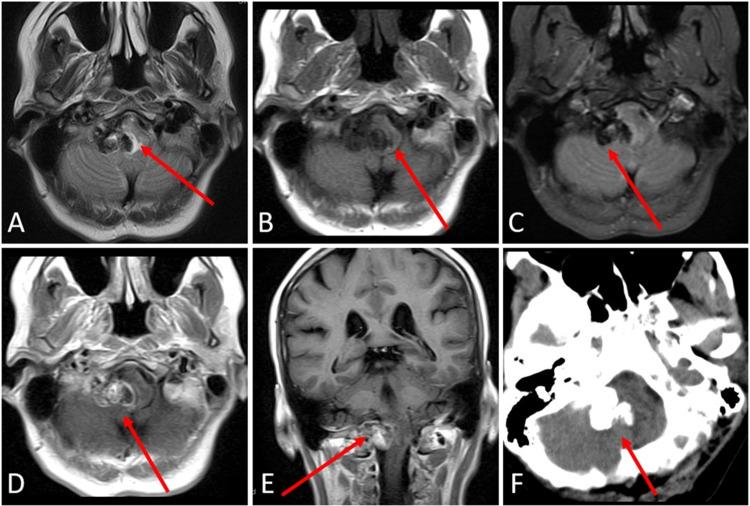

Calcifying pseudoneoplasm of the neuraxis are rare fibro-osseous lesions that can occur throughout the central nervous system. This paper reports one case of this lesion within the posterior fossa and contains a literature review of all cases documented within the posterior fossa to date. A 53-year-old female patient with a history of epiphora, facial irritation, and headaches was found to have a mass centered in the posterior fossa. The patient underwent surgical resection for removal of the mass. Upon review by pathology, the final diagnosis was consistent with calcifying pseudoneoplasm of the neuraxis.

神经轴索的钙化性假肿瘤是罕见的纤维骨性病变,可发生于整个中枢神经系统。本文报告了1例后颅窝内的该病变病例,并对迄今为止后颅窝内记录的所有病例进行了文献综述。一名有溢泪、面部刺激感和头痛病史的53岁女性患者被发现后颅窝有一肿块。该患者接受了手术切除肿块。经病理检查,最终诊断为神经轴索钙化性假肿瘤。